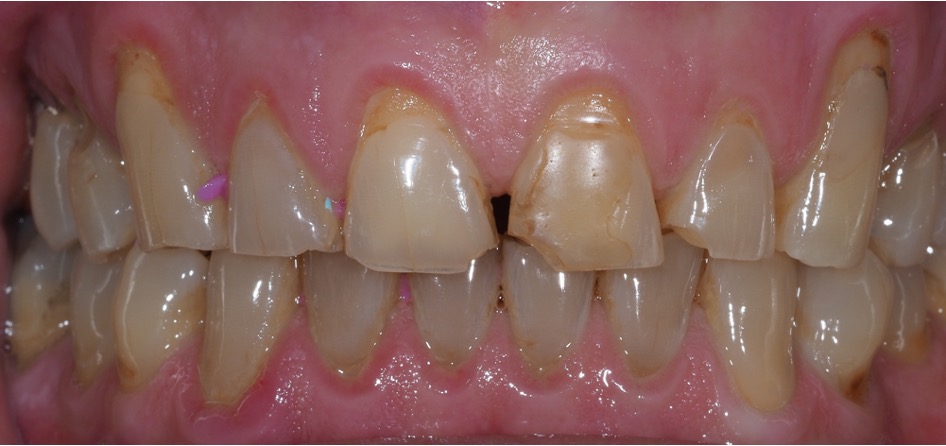

Direct composite is often used to treat toothwear. It is a minimally invasive method that does not damage the underlying tooth structure. It can chip, stain and fail. However, replacement and repair is more straightforward. This case was treated with direct composite alone.

Another case of mild toothwear and discolouration was treated with direct composite bonding.